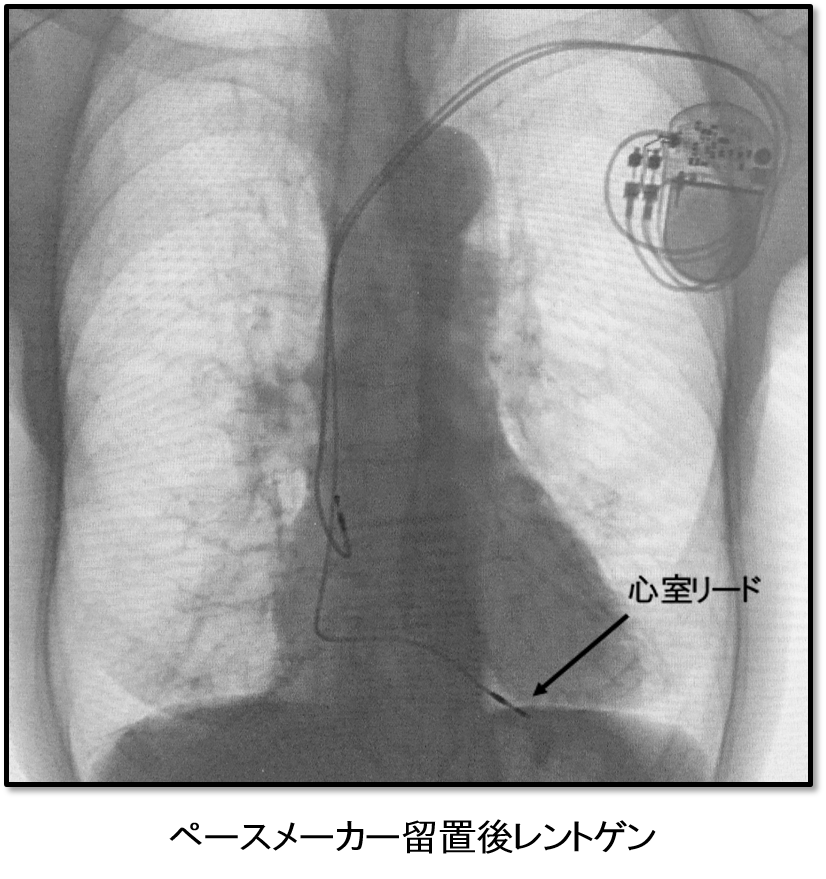

ペースメーカー植え込み術

ペースメーカーが必要になる不整脈のおもな病気は徐脈を来す状態で、1分間の脈拍数が30代になったり、5秒前後心臓が止まったりすると、運動能力が落ちて息切れが起こったり、脳に必要な血液量を送れなくなり、意識喪失に至るケースもあります。